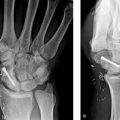

Obtain high-quality radiographs of hand: three views (Postero-anterior, lateral, oblique)

Obtain films of contralateral hand to serve as a template for baseline normal anatomy

Obtain films of initial injury whenever possible

Pathoanatomy of Malunion

Identify the site and direction (rotational, angular, shortening) of the malunion